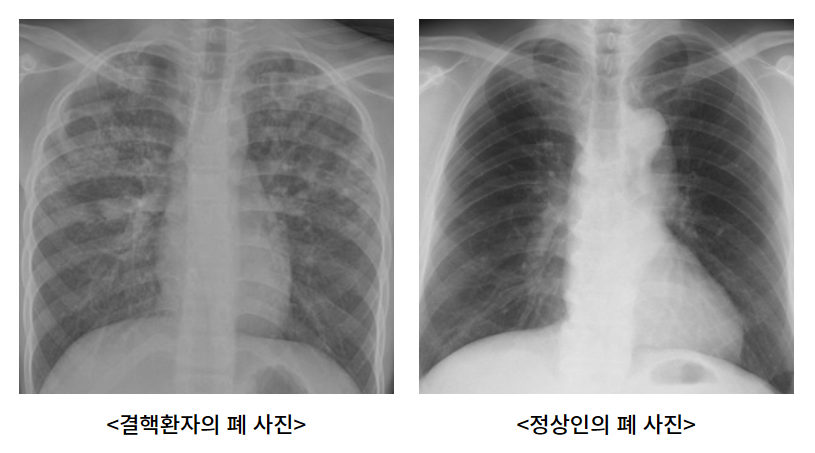

사전에 홍보를 통해 일정과 장소를 안내한 후, 이동 검진 차량이 현장에 배치됩니다. 흉부 X선 촬영을 통해 환자의 폐 상태를 확인한 후, 실시간 원격 판독을 실시하여 결핵 의심 여부를 판단합니다.

이 과정에서 결핵이 의심되는 소견이 발견되면, 추가적인 진단을 위해 가래 검사를 진행하게 됩니다. 이를 통해 정확한 진단과 적절한 치료를 위한 기초 자료를 확보할 수 있습니다.